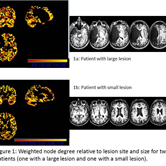

Introduction. There is recent evidence that suggests that resting-state abnormalities in chronic stroke likely influence recovery patterns. In this study, we examined resting state networks in 11 patients with post-stroke aphasia (PWA) in comparison to a database of typical resting state-connectivity patterns to identify the relationship between resting state patterns and post-stroke language impairment and recovery. Methods. 11 PWA with left hemisphere strokes and at least four months post onset participated 3D anatomical images were acquired at TE/TR/TI = 3.04/2100/785 ms, flip angle = 13. The resting state fMRI (rs-fMRI) series contained 140 images with TR/TE/#slices/voxel size/slice thickness=3s/30ms/48/3.3125mmx3.3125mmx3.3125mm/3.3125mm with axial slice acquisition. A group of control subjects over the age of 50 were selected from the 1000 Functional Connectomes database (Biswal et al., 2011; http://www.nitrc.org/projects/fcon_1000). The rs-fMRI image series were pre-processed using standard procedures in SPM8. Reduction of noise of non-neural origin was performed using the CompCor method (Behzadi et al., 2007), removing signals related to the leading principal components of voxels from the white matter and CSF. The residual signals were bandpass filtered between 0.01 and 0.08 Hz in order to isolate the low frequency fluctuations. Voxels were masked to select those that are likely to be gray matter (GM), and non GM voxels were discarded from further analysis. Because the brains of PWA are likely to undergo post-stroke functional reorganization, we used a data-driven method to cluster voxels that (i) are spatially contiguous, and (ii) have time series that are correlated above a threshold. The resulting clusters served as nodes in a graph theoretic analysis, with weighted edges determined based on: i) the Pearson correlations between the mean cluster time series, and (ii) Partial correlations determined using a regularized version of the inverse covariance matrix (e.g., Friedman et al., 2008). Results. To test the hypothesis that there will be shifts in “network hubs” due to post-stroke recovery, we calculated the weighted node degree (sum of all edge weights impinging on a node / cluster) and betweenness centrality (the fraction of the shortest paths between all nodes in the graph that pass through that node) for each cluster, in both PWA and controls. Initial results show an increase in the average number of shortest paths that traverse each cluster in the graph in PWA relative to controls. Figure 1a and 1b show two examples of patient node degree maps, indicating shifts in network hubs (i.e., nodes with particularly high degree and/or betweenness centrality). To test the hypothesis that functional connectivity networks in PWA show decreased efficiency relative to controls, we calculated the global graph efficiency, defined as the inverse of the harmonic mean of the shortest path lengths between all nodes, for each subject. Initial results show a general pattern of reduced global efficiency in PWA relative to controls. Conclusions. Relative to controls, these results indicate inefficiencies in the post-stroke resting-state network, with greater shifts in network hubs in PWA dependent on the site and size of lesion. Such graph analytic results may prove informative in advancing individual-specific therapies.

Figure 1